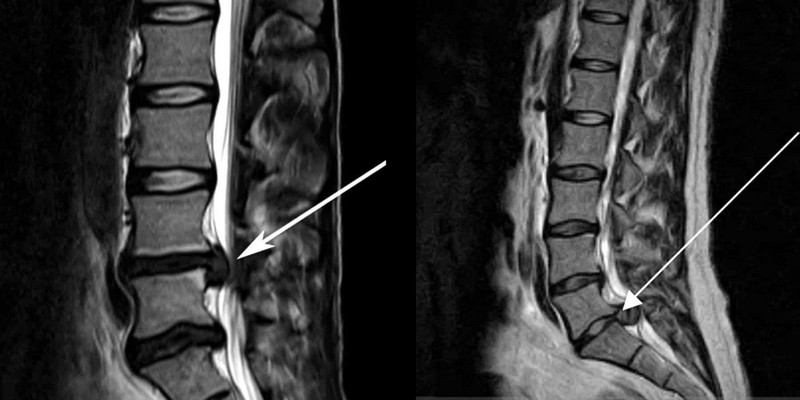

- протрузия и смещение межпозвоночных дисков (грыжа);

- оценка степени, направления и характеристик грыжевого выпячивания.

Для получения детального изображения поясничного и крестцово-копчикового отдела позвоночника используется магнитно-резонансная томография (МРТ). Этот метод позволяет выявить различные аномалии и заболевания:

Время, необходимое для расшифровки и печати снимков, варьируется от 30 минут до целого дня. Явно выраженные заболевания, такие как протрузия, грыжа и остеохондроз, могут быть диагностированы за 15 минут. Оценка онкологического процесса с метастатическим инфильтратом может занять до 6 часов.